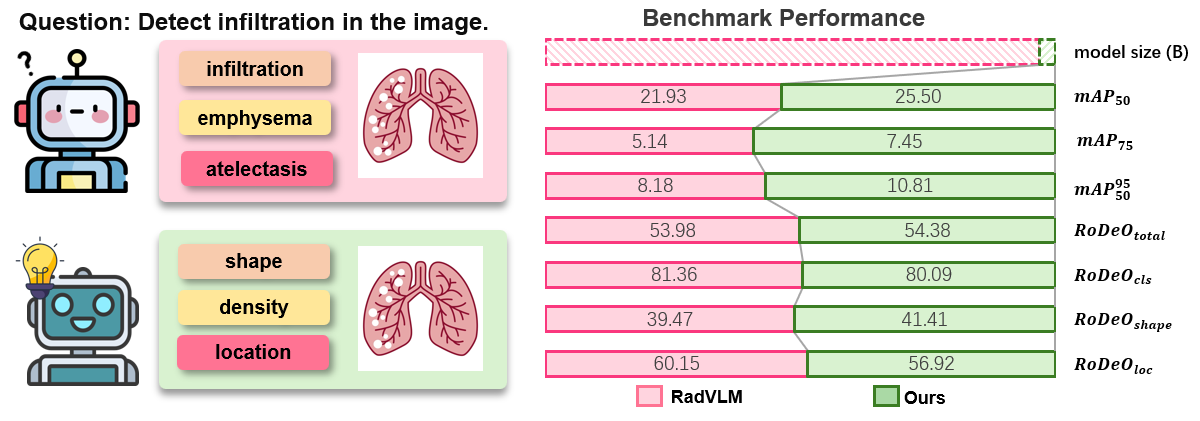

Jun Li, Che Liu, Wenjia Bai, Rossella Arcucci, Cosmin I. Bercea, Julia A. Schnabel.

[paper]

[project]

[huggingface]